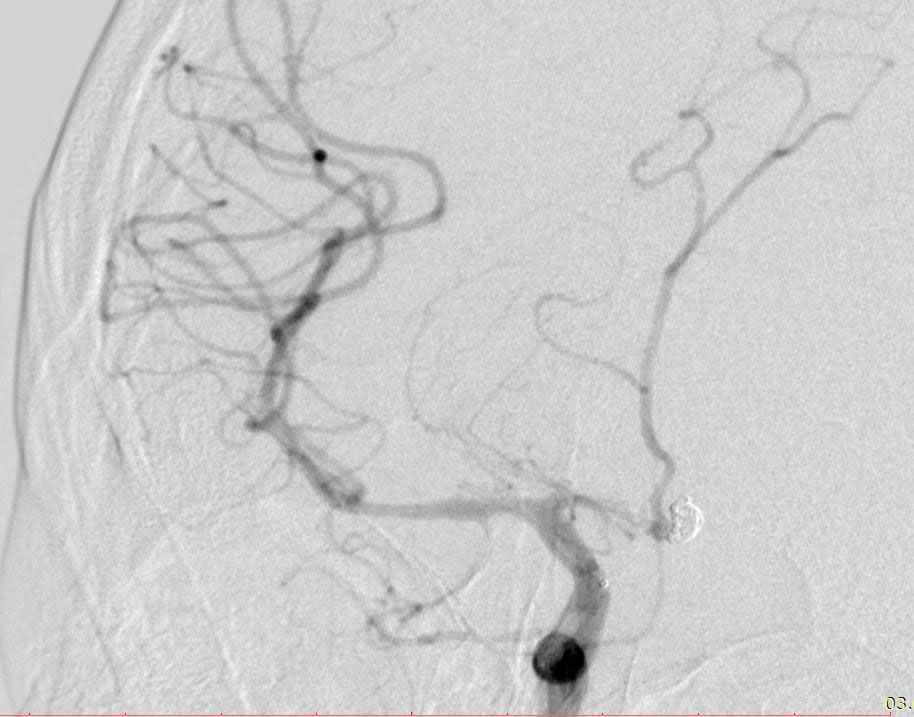

3.05.23 у КНП «ТОКПНЛ» ТОР вперше власними силами була емболізована аневризма судин головного мозку. В результаті розриву аневризми хворий К, 45 років отримав крововилив у мозок. Єдиний шлях лікування такої патології – це виключення аневризми (мішечку у стінці мозкової судини). Ендоваскулярний спосіб до зволяє зробити це без розрізів, безпечно, швидко та надійно. Через прокол на стегні пацієнту було заведено катетер у стегнову артерію та виконано ангіографію – знімок судин головного мозку, де була виявлена аневризма, а також важке ускладнення субарахноідального крововиливу: вазоспазм – звуження просвіту судин головного мозку іноді до повного зупинення кровотоку.

Операція була проведена за допомогою ендоваскулярної емболізації — це мінімально інвазивний метод, який не вимагає відкритого хірургічного втручання на мозку. Через артерію, зазвичай у стегні, лікар вводить тонкий катетер, який проводить безпосередньо до аневризми.

Під час цієї процедури у порожнину аневризми було введено спеціальні спіралі з пам'яттю форми (койли). Ці мікроспіралі скрутилися, утворивши щільний клубочок, що заповнив аневризму та запобіг повторній кровотечі. Додатково була виконана фармангіопластика — введення препаратів для зняття спазму судин, що дозволило безпечно дістатися до ураженої ділянки.

Ця складна операція стала можливою завдяки сучасному ангіографу Siemens Artis One, який надає хірургам чітке зображення судин у реальному часі. Але найголовніший фактор успіху — це злагоджена робота усієї операційної бригади: досвідчених нейрохірургів, анестезіологів, навчених медичних сестер та інших фахівців.